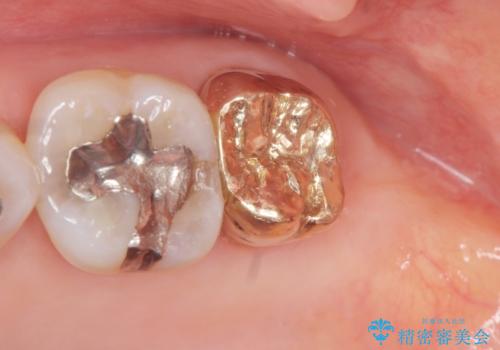

クラウンの将来的な虫歯の再発を防ぐために周囲の歯ぐきを切除することで歯の高さを出し安定した歯周環境にしたのち噛み心地の良いゴールドクラウンを製作します。

クラウンを装着した歯の虫歯の再発を防ぎ長い予後を期待するために削った箇所をしっかりとかぶせる適合の良さが必要はもちろんですが、セメントの漏洩を防ぐためにクラウンの十分な支台高径を歯周外科を行い獲得しました。

PGA(ゴールド)クラウン、インレーの注意事項(リスク・副作用など)